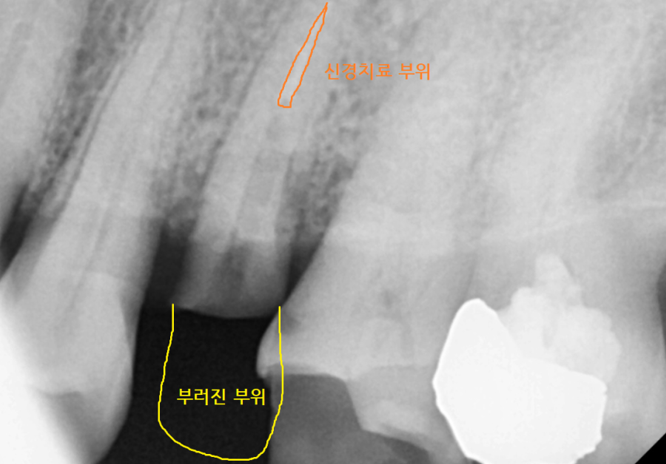

강일동 치과 처음 내원하셨을 때 찍어놓은 사진입니다.

치아 부러짐 부위 딱! 보이죠~?

생각보다 많이 부러졌네요~

231211

부러진 부위가 머리 부분 대부분을 차지했습니다.

부러진 부분도 크고

신경치료도 되어있는 흔적이 보였습니다.

그동안의 경험을 보았을 때 살리기 어려워

발치하시는 것을 조심스레 말씀드렸는데요.